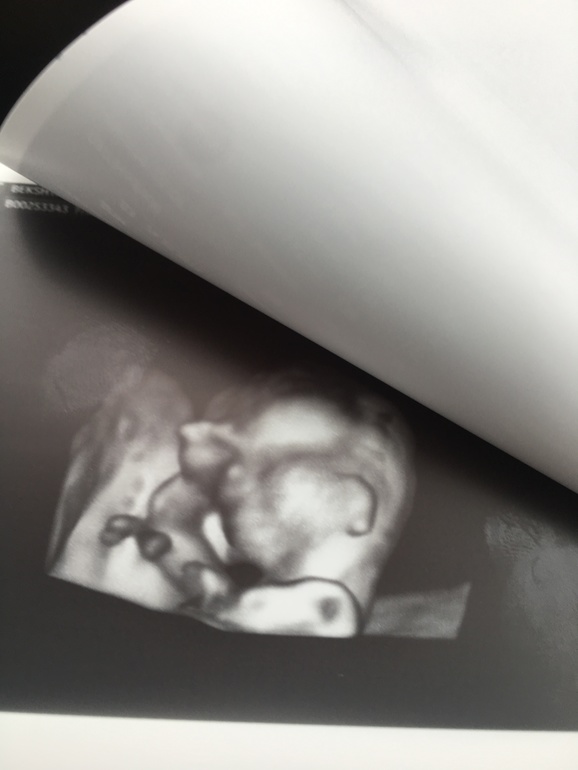

Это фото: мояяя прелееесть))))лапти скрестила свои)

РУЧКА! Пап, дай пять